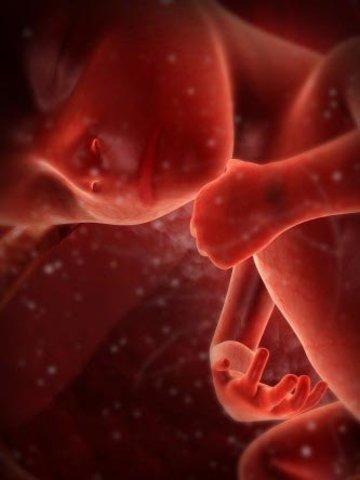

• 4a SEMANA-PRIMER MES

4a SEMANA-PRIMER MES

Durante la 4a semana (1er mes) el embrión mide 4mm de longitud desde el extremo de la cabeza hasta el talón. Cada día la longitud aumenta 1mm hasta el día 55 de gestación. Después crece 1,5mm diario. Comienzan los esbozos de las extremidades, la boca y las mandíbulas son visibles.